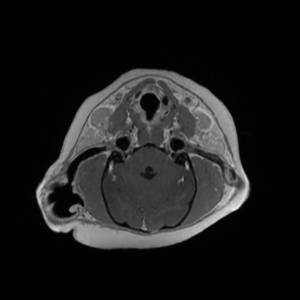

Main Gallery

Playing with a photo gallery function. It is possible to have multiple galleries, each within a namespace.